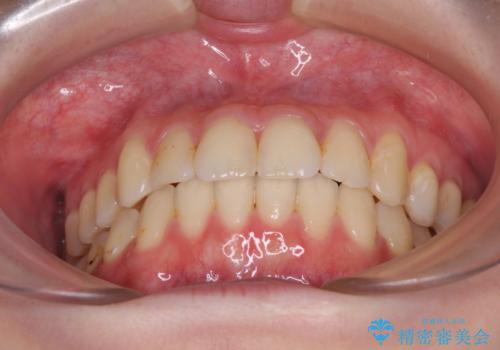

- 上下前歯のデコボコを気にして来院された患者様です。

以前矯正をした後戻りということで、歯列不正はそれほど大きくなかったため、インビザライン・ライトを用いて矯正治療を行うこととしました。

前歯のデコボコが残っており、シミュレーション通りに動いていない部分がありましたが、再矯正であることやご本人の満足いくところまでデコボコが改善されたとのことで、治療を終了することとしました。